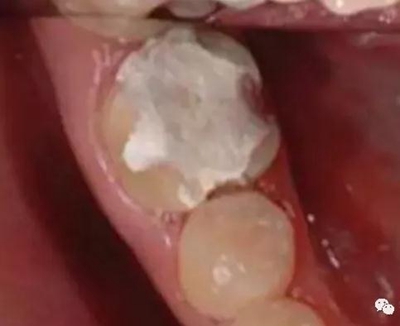

4. 預(yù)留修復(fù)體的空間

5. 邊緣的適合性